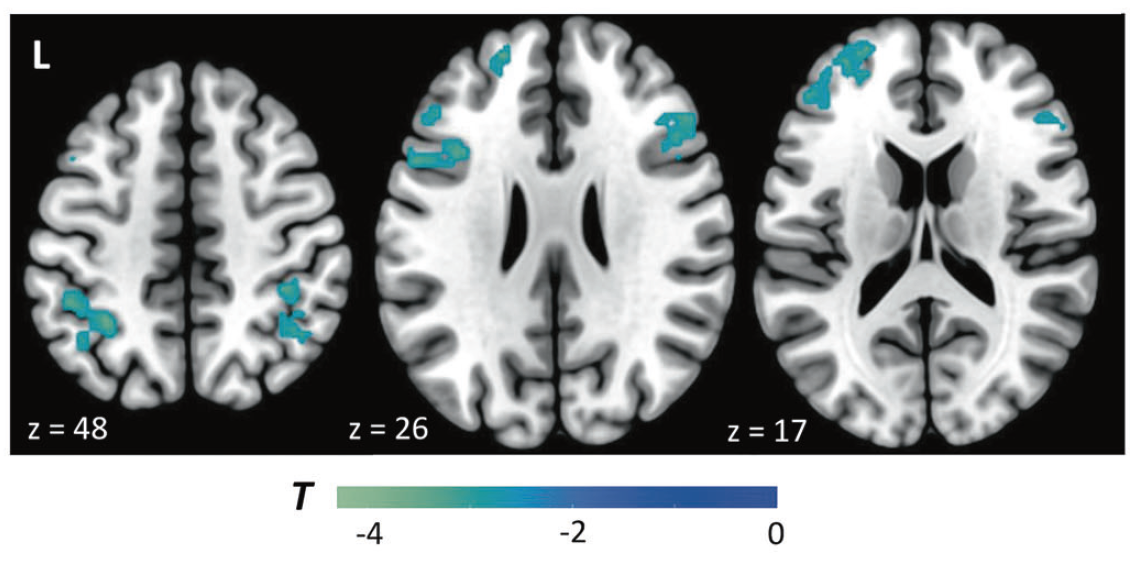

Post-traumatic stress disorder (PTSD) leads to impairments in both cognitive and affective functioning. Animal work suggests that chronic stress reduces dopamine tone, and both animal and human studies argue that changes in dopamine tone influence working memory, a core executive function. These findings give rise to the hypothesis that increasing cortical dopamine tone in individuals with greater PTSD symptomatology should improve working memory performance. In this pharmacological functional magnetic resonance imaging (fMRI) study, 30 US military veterans exhibiting a range of PTSD severity completed an emotional working memory task. Each subject received both placebo and the catechol-O-methyl transferase inhibitor tolcapone, which increases cortical dopamine tone, in randomized, double-blind, counterbalanced fashion. Mnemonic discriminability (calculated with d’, an index of the detectability of working memory signals) and response bias were evaluated in the context of task-related brain activations. Subjects with more severe PTSD showed both greater tolcapone-mediated improvements in d’ and larger tolcapone-mediated reductions in liberally-biased responding for fearful stimuli. FMRI revealed that tolcapone augmented activity within bilateral frontoparietal control regions during the decision phase of the task. Specifically, tolcapone increased cortical responses to fearful relative to neutral stimuli in higher severity PTSD subjects, and reduced cortical responses to fearful stimuli for lower severity PTSD subjects. Moreover, tolcapone modulated prefrontal connectivity with areas overlapping the default mode network. These findings suggest that enhancing cortical dopamine tone may represent an approach to remediating cognitive and affective dysfunction in individuals with more severe PTSD symptoms.